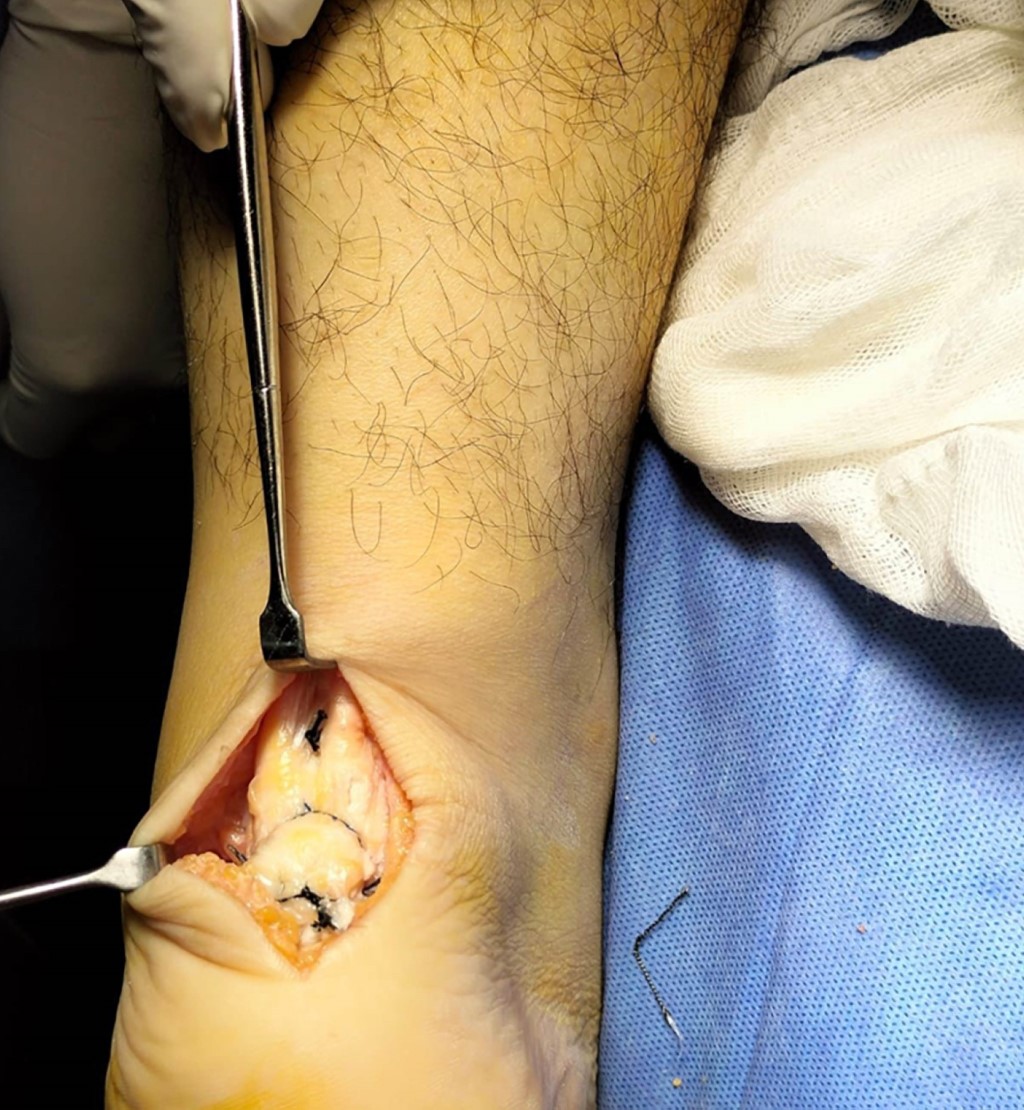

La técnica quirúrgica fue realizada con isquemia utilizando venda tipo Smarch, con incisión en S itálica mediante abordaje posterior tomando como referencia borde lateral de tendón aquíleo de 10 centímetros de longitud. Se disecó por planos hasta llegar a entesis, desinsertando de esa región el tendón aquíleo. Se observó tejido fibroso, se desbridó y posteriormente se realizó osteotomía de 10 milímetros, se colocaron dos anclas de 3.5 milímetros tape con agujas a 20 milímetros de distancia entre ellas y se suturó con puntos simples al cabo libre del tendón del tríceps sural. Su tunelizó borde posterior de calcáneo con broca 3.5, sosteniendo de forma temporal tendón con clavillos Kirschner. Se traspasó FiberTape con sistema Percutaneous Achilles Repair System (PARS) proximal a las suturas con técnica antidesgarro, fijando el mismo con anclas SwiveLock 2.5 milímetros (Figura 4).8 Por último, se suturaron bordes libres de tendón calcáneo con sutura de alta resistencia (Figura 5).9 Se realizaron movimientos de flexoextensión del tobillo corroborando adecuada resistencia de éste. Se corroboró adecuada colocación del material bajo fluoroscopia transquirúrgica (Figura 2).10 Se realizó hemostasia y se cerró herida con vicryl 1-0, 2-0 para tejido celular subcutáneo y nylon 3-0 para piel. Se retiró isquemia y se colocó férula suropodálica anterior en equino.

Figura 5